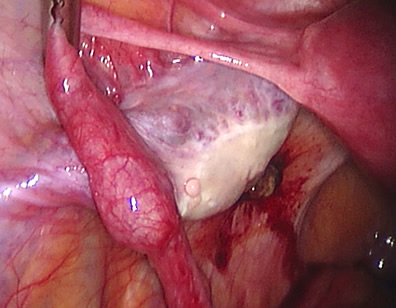

This lady had an ectopic pregnancy in the left tube. See the dilated area in the tube.